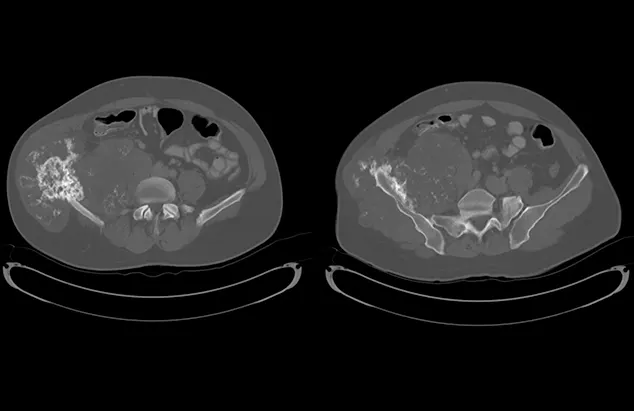

FIGURE 1

Axial (A) and coronal (B) CT images from the patient. An aggressive bone lesion arising from the left ilium, with extension to the surrounding soft tissues, can be seen.

Diagnosis

CBC, serum chemistry profile, and urinalysis results were unremarkable. Three-view thoracic radiographs showed no evidence of gross metastatic disease. A CT scan of the chest, abdomen, and pelvis showed an aggressive bone lesion of the left ilium, compatible with osteosarcoma, with tumor extension to the surrounding soft tissue (Figure 1). A full-body bone scan was performed. Static images were obtained 2 hours after intravenous injection of Tc99m-MDP. There was marked uptake in the area of the primary tumor (ie, the left ilium). There was also a possible metastatic lesion in the left costal cartilages; however, careful review of the CT scan showed that the increased uptake of radiopharmaceutical at that site was most likely consistent with old trauma rather than metastatic disease (Figure 2).